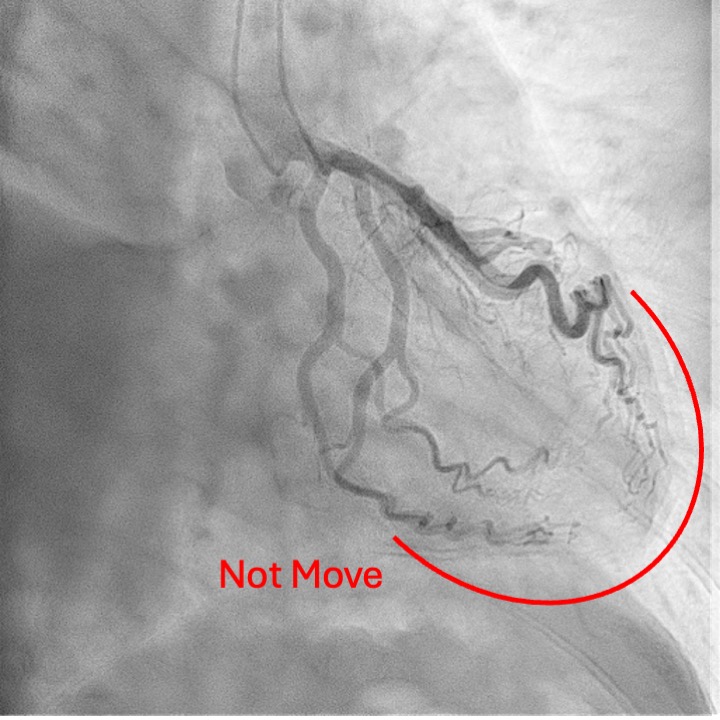

Coronary angiography revealed a distinctive finding in which the vessels and branches covering mid- to apical region of the left ventricle did not completely move in conjunction with the cardiac cycle, while those covering basal-part myocardium and running along left atrioventricular groove remain synchronized with the heart motion. This unusual finding was explained by the hard-and-fixed pericardium firmly adhered to the myocardium constraining the pulsation of the relevant part of the coronary tree. (Fig7-8) To obtain a more detailed anatomical and functional assessment, cardiac computed tomography (CT) was performed. The CT study further confirmed the absence of the usual counterclockwise rotational motion of the left ventricular apex during systole, a finding that was in complete agreement with the previously observed coronary angiographic pattern. In addition, the imaging revealed impaired diastolic filling of both ventricles, diffuse pericardial thickening, and signs of pericardial adherence, all consistent with the diagnosis of constrictive pericarditis.

Case Summary